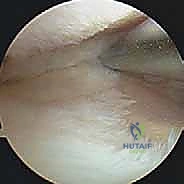

لفهم أهمية عملية (HTO)، يجب أولاً فهم كيف تعمل الركبة. مفصل الركبة يتحمل وزن الجسم بالكامل تقريباً أثناء المشي والوقوف. ينقسم المفصل إلى ثلاث حجرات رئيسية: الحجرة الداخلية (الإنسية)، الحجرة الخارجية (الوحشية)، وحجرة الرضفة (الصابونة).

في الحالة الطبيعية الميكانيكية، يمر "محور تحمل الوزن" (Weight-bearing axis) مباشرة عبر منتصف الركبة، مما يوزع الضغط بالتساوي. ولكن، عند حدوث تقوس في الساقين (Varus Deformity)، ينزاح هذا المحور إلى الداخل، مما يضع ضغطاً هائلاً ومدمراً على الغضروف الداخلي للركبة.

هذا الضغط المستمر يؤدي إلى تآكل الغضروف بشكل أسرع من الطبيعي، مما يسبب احتكاك العظم بالعظم، وهو ما يُعرف بخشونة الركبة. هنا يأتي دور الجراحة لإعادة توجيه هذا المحور نحو الجزء الخارجي السليم من الركبة.

- حالة المفصل: يجب أن تكون الخشونة مقتصرة على حجرة واحدة فقط (غالباً الداخلية)، مع وجود غضروف سليم في الحجرة الخارجية.